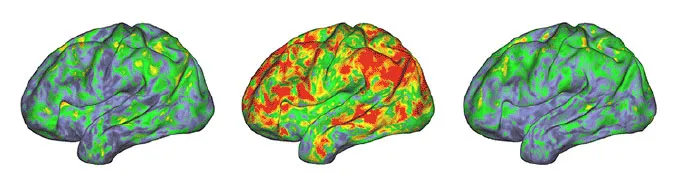

Brain imaging data show small everyday changes in brain activity in a single person (green and yellow colors). After a dose of psilocybin, activity changes dramatically as neural collectives fall out of sync (yellow, orange and red). After the drug wears off, activity returns to normal.

Sara Moser/Washington University

The psychedelic drug psilocybin dramatically changes how collections of nerve cells work in the brain, eliminating normal communication between brain regions, a new brain scanning study published July 17 in Nature shows. These brain images, taken before, during and after a high dose of psilocybin, expand the understanding of the drug’s effects, which is being studied for its promise in treating mental health disorders such as depression.